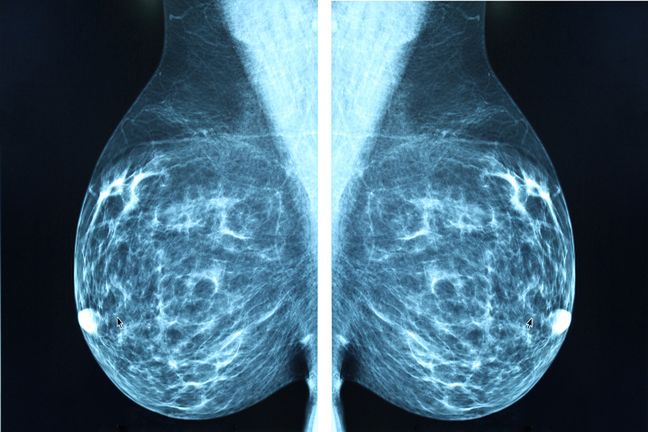

Gęstość piersi

Piersi połowy z nas mają strukturę gęstą. Oznacza to, że mamy więcej tkanki gruczołowej i włóknistej, co może sprawiać trudności podczas odczytu wyników badań mammograficznych. Zarówno zmiany w postaci guzków, jak i nagromadzenia włókien i gruczołów na obrazie mammografii będą wyglądały jednakowo. Kobiety z gęstszą strukturą piersi są też bardziej narażone na rozwój raka piersi, dlatego powinny położyć większy nacisk na profilaktykę i regularne wykonywanie badań.

Regularnie wykonywana mammografia pozwoli odpowiednio wcześnie wykryć wszelkie zmiany w postaci guzków w piersiach